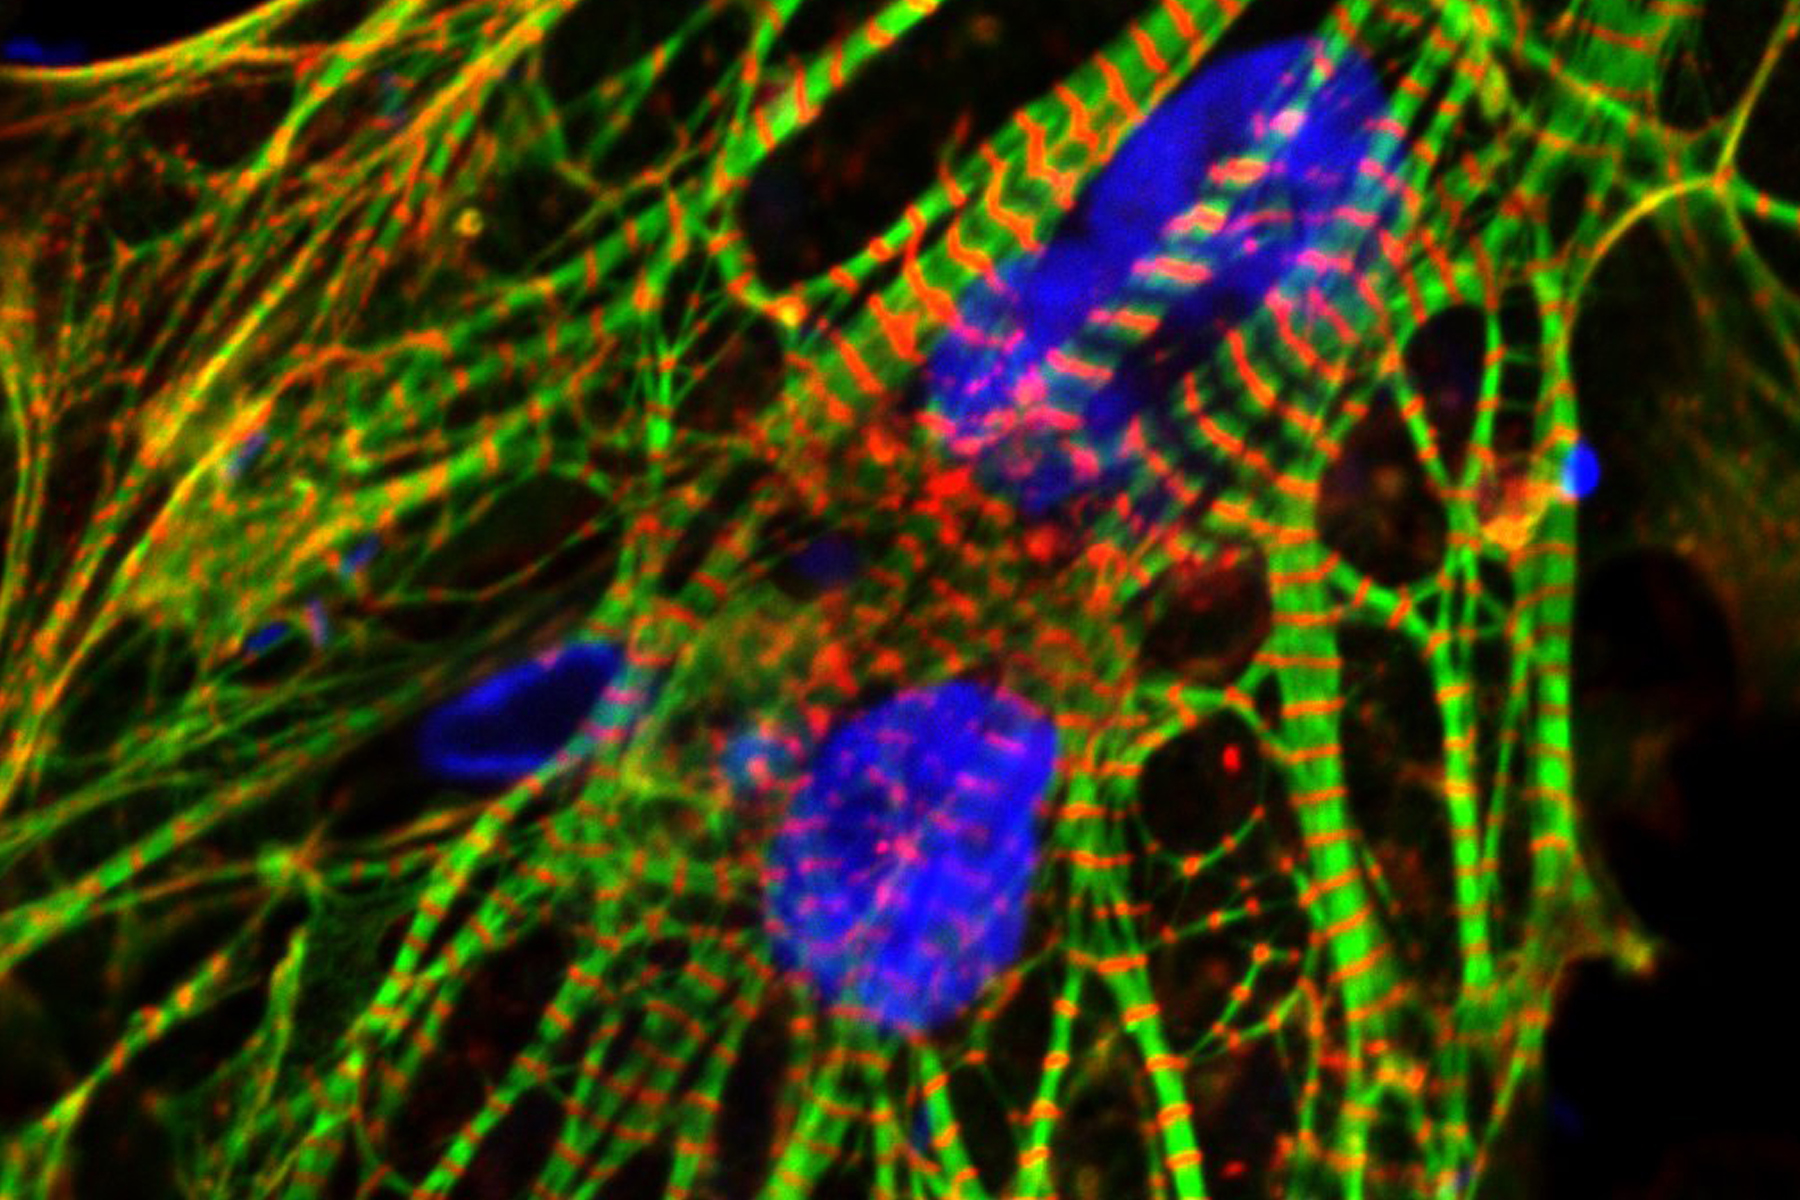

Human Induced Pluripotent Stem Cell derived Heart Cells cardiom UIC

A Heartbeat In A Dish Growing Specialized Heart Cells

Heart Regeneration After Reprogramming Of Cardiac Muscle Cells